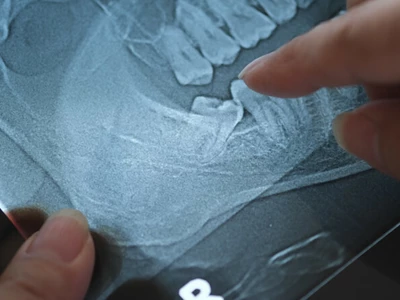

사랑니는 20대 전후에 맹출되지만, 매복되거나 부분적으로만 보이는 경우가 많아 주기적인 검진이 필요하다. 사랑니에 충치, 염..